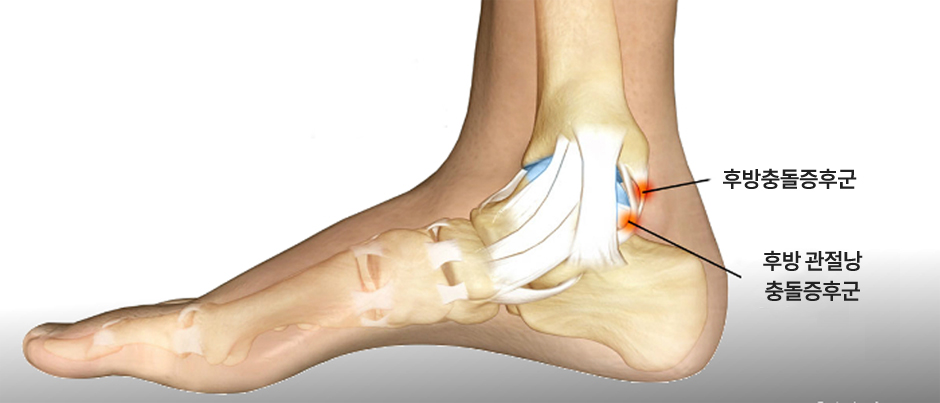

후방충돌증후군(삼각골증후군)은 발목뼈 뒤쪽에 분리되어 있는 뼈조각과

그 뒤를 지나가는 힘줄이 충돌하면서 염증이 발생하는 질환!

최소침습 발목 후방내시경술

내시경을 이용하여 긴 절개 없이 최소침습으로 치료!

염증, 충돌을 일으키는 뼈조각만 선택적 제거!